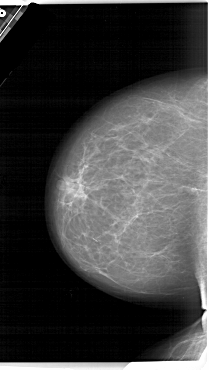

A_1464_1.LEFT_CC

LEFT_CC LINES 6646 PIXELS_PER_LINE 3751 BITS_PER_PIXEL 12 RESOLUTION 43.5 NON_OVERLAY